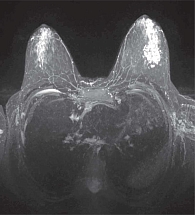

Рис. 6. УЗ-признаки фиброзно-кистозной мастопатии у 17-летней пациентки

УЗИ показывает расширение протоков, утолщение связок Купера, мелкозернистую гетерогенность железистой ткани, возможные анэхогенные кисты, ЦДК – тенденцию к гиповаскуляризации. При узловом варианте очаги пониженной эхогенности без четкого ободка, с элементами локального фиброза [6, 7, 16] (рис. 6).